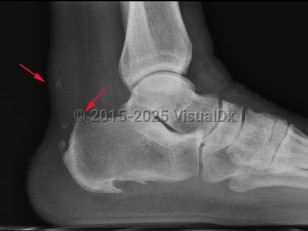

Achilles tendonitis